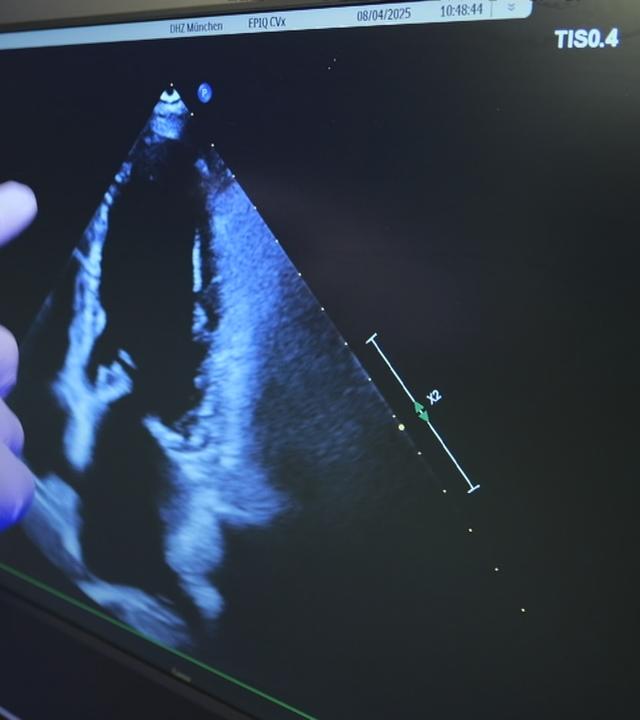

Ultraschallbild

Die Takotsubo-Kardiomyopathie, auch als „Broken-Heart-Syndrom“ bekannt, ist eine akute, lebensbedrohliche Erkrankung, bei der Symptome eines Herzinfarkts auftreten. In etwa zehn Prozent der Fälle führt sie zu einer schweren Herzinsuffizienz, an der rund die Hälfte der Betroffenen stirbt.